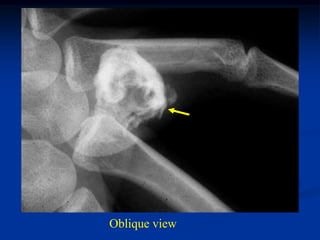

Periosteal chondroma

33 year female with periosteal chondroma and

enchondroma in same ray

Oblique view